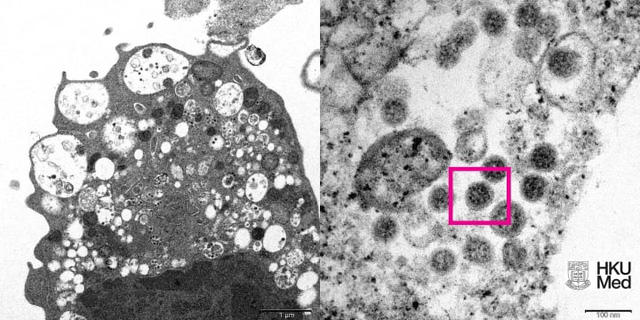

Ngày 8/12, các nhà khoa học tại trường Đại học Hong Kong đã công bố hình ảnh đầu tiên về biến thể Omicron dưới kính hiển vi điện tử.